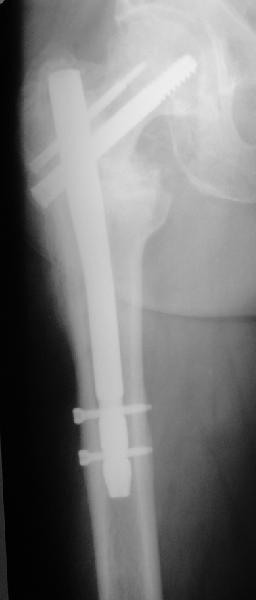

Больная 61 год. Травма 1 год назад – закрытый базальный перелом бедренной кости без смещения. Перелом рентгенологически был диагностирован только через 6 недель (на первичных снимках не визуализировался, КТ не проводилось, повторную травму отрицает). Проведен курс консервативного лечения (ходьба на костылях без опоры на левую ногу до 4-х месяцев, ЛФК, физиолечение и т.п.).В настоящее время передвигается при помощи костылей с незначительной опорой на левую ногу. Больная страдает сахарным диабетом.Возможные варианты лечения: 1) Тотальное эндопротезирование.2) Ревизия ложного сустава, возможно костная пластика, МОС углообразной пластиной 130, DHS, AFN.

Закрытый интрамедуллярный остеосинтез или он же в сочетании с чрескожной межвертельной остеотомией в случае внесуставного несращения - это, по сути, эндопротезирование с собственной шейкой и головкой бедра. Но через 3-4 разреза по 1,5-2 см. Нога сразу опорная, сустав конгруэнтный - чего еще надо? В приложении - похожее несращение тоже у пациента за 60 и с диабетом 2 типа...

Важно достигнуть хорошую ротационную стабильность фиксации. Угловая V-образная пластинка стабильнее , а еще лучше два винта. Проксимальный бедренный гвоздь с двумя винтами - PFN, Syntes или любой похожий по моим понятиям лучший вариант.